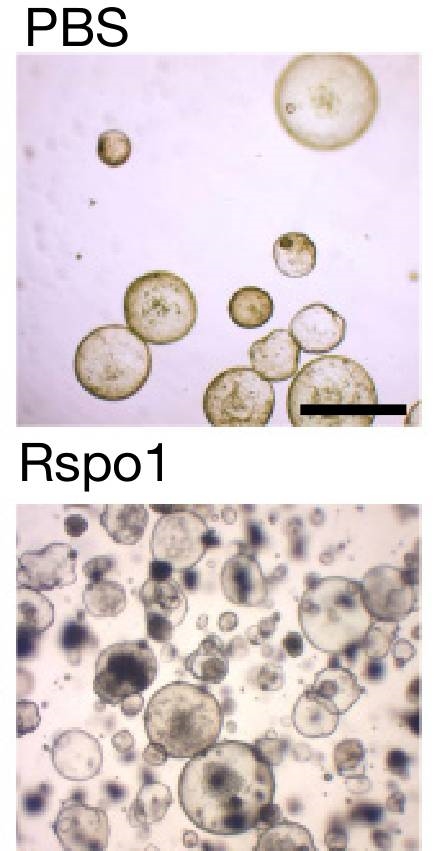

هڈ¯وک¯�,�,�,�,Meyerهچڑه£«هڈ‘وکژ�,�,�,�,è؟™ن¸¤ç§چ细èƒه¯¹WNTé€ڑè·¯çڑ„هڈچه؛”وک¯ه·®هˆ«çڑ„م€‚�م€‚م€‚و£ه¸¸Rspoن½œç”¨ن؛ژهˆ†è§£و°´ه¹³ن½ژ�,�,�,�,ه¢و®–较ه؟«çڑ„ه¹²ç»†èƒهœ¨هگژ�,�,�,�,ن¼ڑن½؟ه¹²ç»†èƒçڑ„ه¢و®–é€ںçژ‡وک¾è‘—هٹ é€ں�,�,�,�,ه¯¼è‡´ه…¶ه¤ھè؟‡ه¢و®–م€‚�م€‚م€‚而Rspoن½œç”¨ن؛ژه¢و®–较و…¢çڑ„细èƒهگژ�,�,�,�,ن¼ڑوک¾è‘—وٹ‘هˆ¶ه…¶ه¢و®–م€‚�م€‚م€‚

Rspoن¼ڑوک¾è‘—ه¢ه¼؛و•ڈو„ںه¹²ç»†èƒçڑ„و‰©ه¢é€ںçژ‡ï¼ˆهچ•ç»†èƒن½œè‚²24ه°ڈو—¶ï¼‰

و£ه¦‚Sigalهچڑه£«و‰€è¯´�,�,�,�,“ç”±ن؛ژه¹½é—¨è؛و†èڈŒه¼•èµ·ç†ڈوں“وœ؛ن½“و— و³•è‡ھوˆ‘و²»و„ˆ�,�,�,�,ه› و¤�,�,�,�,若ن¸چو²»ç–—�,�,�,�,ه¹½é—¨è؛و†èڈŒهڈ¯èƒ½وپ’ن¹…ن¸€è؟هˆ؛و؟€é—´è´¨وˆگç؛¤ç»´ç»†èƒو¸—é€ڈRspoو¥هˆ؛و؟€ه¹²ç»†èƒç ´ç¢ژ�,�,�,�,è؟™ن¹ں许足ن»¥è¯ é‡ٹن¸؛ن»€ن¹ˆه¹½é—¨è؛و†èڈŒç†ڈوں“ن¼ڑوک¾è‘—ه¢و·»èƒƒç™Œهچ±ه®³ï¼ˆ10)م€‚�م€‚م€‚”